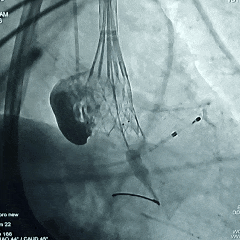

瓣膜工作位多角度评估

瓣膜稳定脱钩

瓣膜脱钩后造影,瓣膜形态不佳决定后扩张